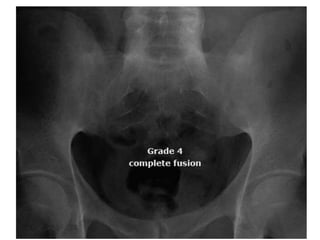

• The SI joint abnormalities are typically graded

to identify the nature and severity of

• Grade 4: total ankylosis of joints

• The SIjoint abnormalities are typically graded to identify the nature and severity of involvement. • Grade 0 : Normal. • Grade 1: Suspicious(but not definite) changes • Grade 2: minimal abnormality- small areas of erosions or sclerosis without alteration of joint width.

• Grade 3:unequivocal abnormality – moderate or advanced sacroilitis with one or more of the following: erosions, sclerosis, joint space widening, narrowing, or partial ankylosis. • Grade 4: total ankylosis of joints